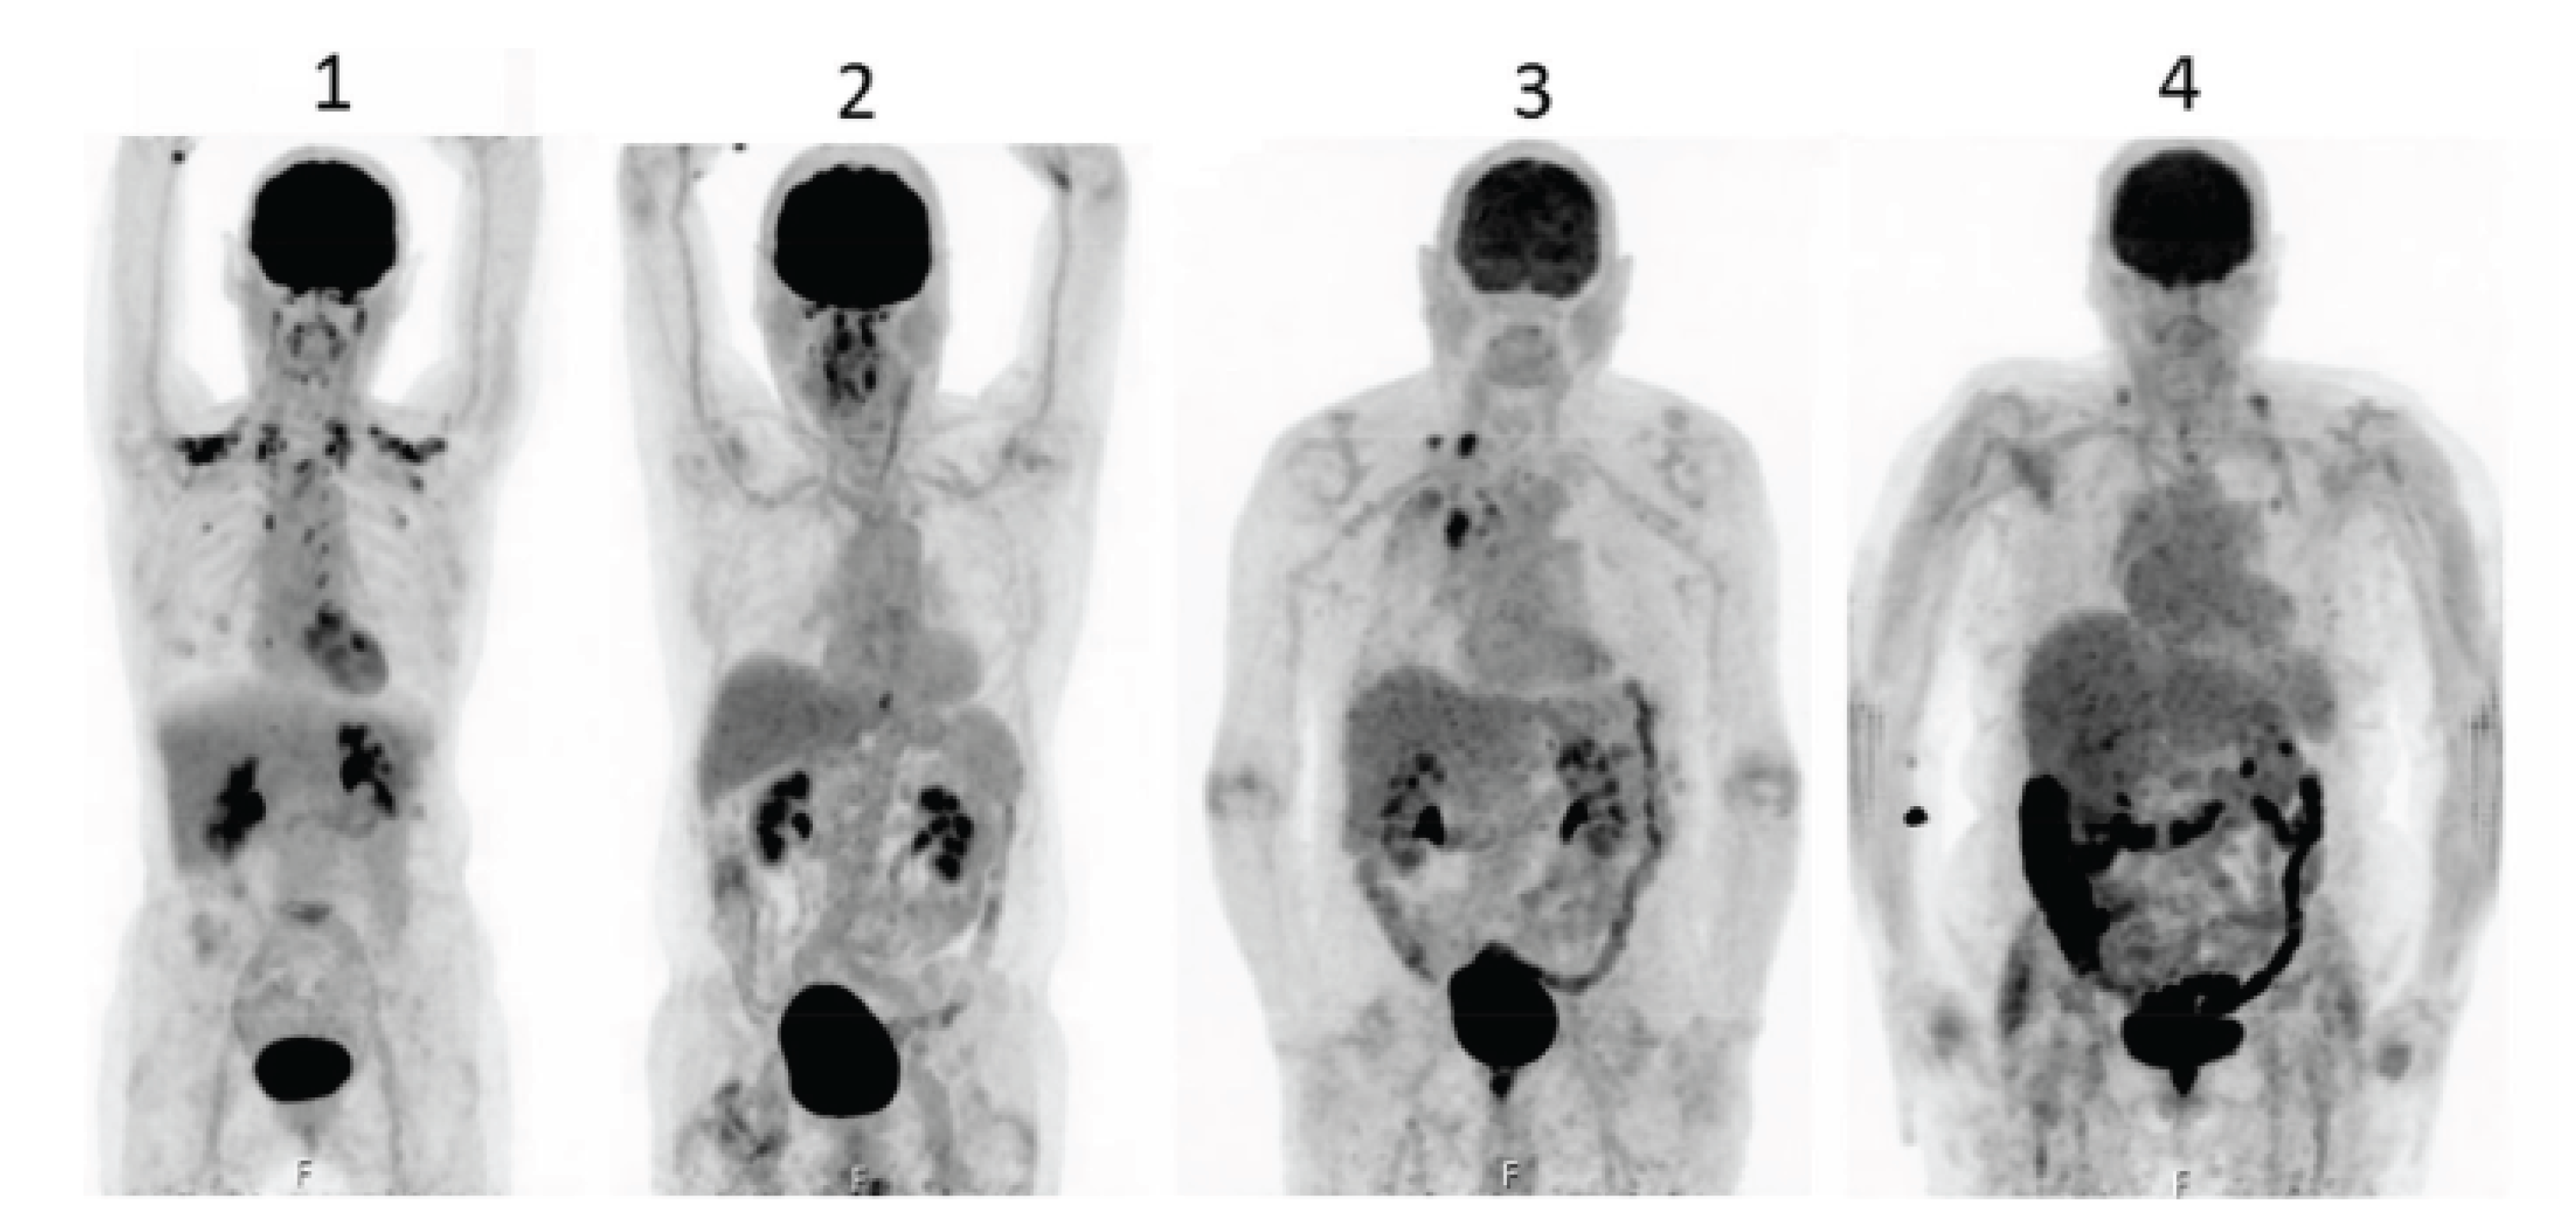

Accumulation of F18-FDG in the large intestine (Figure 4) has been found also in persons who regularly use laxatives [193,194]. SUVmax can even reach levels which simulate those of colorectal neoplasms (Figure 5) in patients with chronic constipation [195].

Figure 4. PET-pictures of early scans (upper row) and of late FDG-scans(lower raw) after oral administration of laxatives. The arrows in the upper row of PET-scans show the different patterns of accumulation of the tracers in the large intestine. From Chen Y-K et al. ([194], with permission).